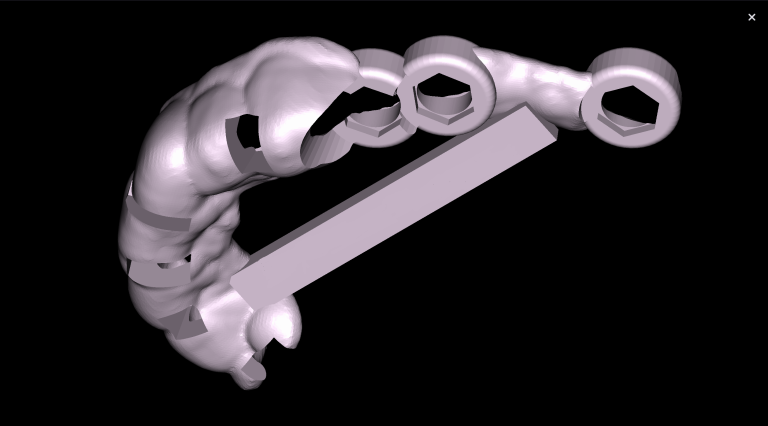

With the help of Diagnocat STL reconstruction, the doctor can visualize changes in the level of bone relative to the roots of the teeth, which are hidden behind the gum.